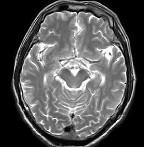

问题 男,头痛7月余,伴左侧面部麻木,疼痛剧烈时伴恶心,无呕吐,请根据所提供图像,选择最可能的诊断()

选项 A.垂体瘤 B.颅咽管瘤 C.生殖细胞瘤 D.脑膜瘤 E.胶质瘤

答案 B